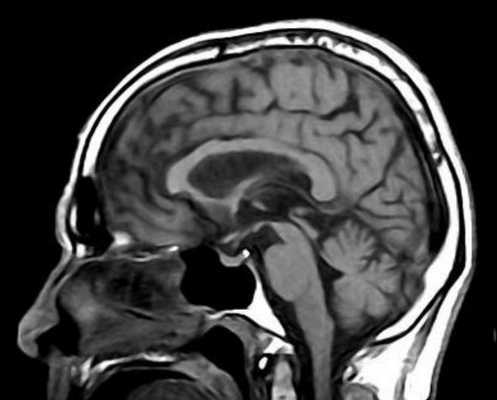

Гипертрофическая дегенерация ядер оливы считается специфической формой транссинаптической гипертрофической дегенерации и развивается вследствие неспецифического повреждения денто-рубро-оливарного пути. Хотя это состояние у детей считается редким, сообщается о его превалировании у пациентов с метаболическими заболеваниями, а также после операции по поводу опухолей задней черепной ямки. На МРТ выявляются Т2-гиперинтенсивные очаги, часто с билатеральным и симметричным увеличением оливарных ядер. Они начинают появляться в течение месяца после острого события и в течение 3-4 лет имеют тенденцию к разрешению.

К посттравматическим изменениям можно отнести гипертрофическую дегенерацию оливкового ядра, которая наблюдается крайне редко чрез 3-6 месяцев после травмы. При МРТ головного мозга выявляется повышенный сигнал на Т2-взвешенных МРТ с одной или двух сторон.

МРТ головного мозга. Т2-взвешенная аксиальная МРТ. Гипертрофическая дегенерация левого оливкового ядра.